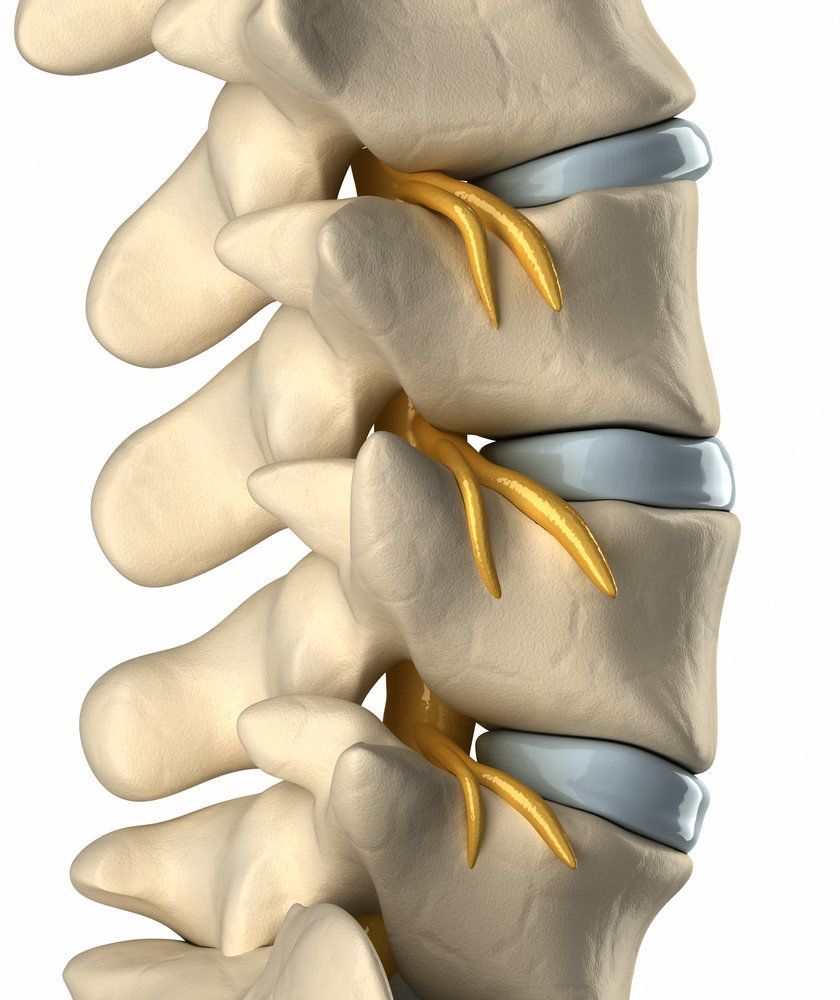

آرتروز گردن

آرتروز گردن یک بیماری وابسته به سن است که بیش از 85 درصد افراد بالای 60 سال را درگیر میکند. این بیماری در مردان و زنان رخ میدهد.

ستون فقرات گردنی در گردن قرار دارد و شامل مفاصل وجهی است. این مفاصل به حفظ انعطافپذیری در ستون فقرات کمک میکنند و دامنه حرکتی را امکانپذیر میکنند. هنگامی که غضروفهای اطراف مفصل شروع به تحلیل رفتن میکنند، در نتیجه آن، آرتروز گردن ایجاد میشود.

آرتروز گردن همیشه علائم ایجاد نمیکند. در صورت بروز، علائم ممکن است از خفیف تا شدید باشد و شامل موارد زیر است:

آرتروز ستون مهرهها

اگر کمردرد دارید، ممکن است به آرتروز ستون مهرهها مبتلا باشید. این شرایط مفاصل وجهی واقع در پایین کمر و باسن را تحت تأثیر قرار میدهد. سن و ضربه به ستون فقرات هر دو عواملی بالقوه در در این آرتروز هستند. زنان بیشتر از مردان به این بیماری مبتلا میشوند. افرادی که دارای اضافه وزن هستند یا مشاغل آنها نیاز به چمباتمه زدن و نشستن دارد نیز ممکن است در معرض خطر بیشتری باشند.

شدت علائم آرتروز نخاعی میتواند متفاوت باشد. آنها عبارتند از:

· سفتی یا حساسیت به لمس در مفاصل پشت

· ضعف، بیحسی یا سوزن سوزن شدن در بازوها یا پاها

· کاهش دامنه حرکت

توجه به این علائم مهم است. در صورت عدم درمان، آرتروز نخاعی میتواند بدتر شود و باعث علائم شدیدتر و ناتوانی شود.